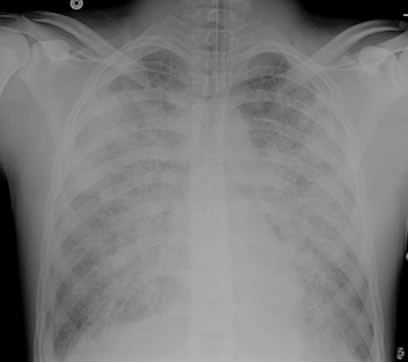

- Imaging – Bilateral opacities not fully explained by effusions, atelectasis, or masses/nodules